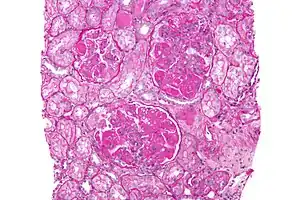

Micrograph image of increased mesangial matrix and mesangial hypercellularity due to diffuse proliferative lupus nephritis

In DPGN Most of the glomeruli show endothelial and mesangial proliferation, affecting the entire glomerulus, leading to diffuse hypercellularity of the glomeruli, producing in some cases epithelial crescents that fill Bowman's space. When extensive, immune complexes create an overall thickening of the capillary wall, resembling rigid "wire loops" on routine light microscopy. Immune complexes can be visualized by staining with fluorescent antibodies directed against immunoglobulins or complement, resulting in a granular fluorescent staining pattern. Electron microscopy reveals electron-dense subendothelial immune complexes (between endothelium and basement membrane). In due course, glomerular injury in DPGN gives rise to scarring (glomerulosclerosis). Most of SLE patients with DPGN have hematuria with moderate to severe proteinuria, hypertension, and renal insufficiency.[2]

A kidney biopsy is the most important diagnostic tool. With a biopsy, the sample will be looked at histologically. With this information, a proper diagnosis can be completed. There are many forms of glomerulonephritis, but under a microscope, DPGN will show increased cell count of polymorphonuclear cells, cellular crescents, and fibrinoid necrosis. A patient with DPGN will have more than 50% of their glomeruli involved.[4][5] If a patient has DPGN, that means they have an active form of glomerulonephritis.[10]